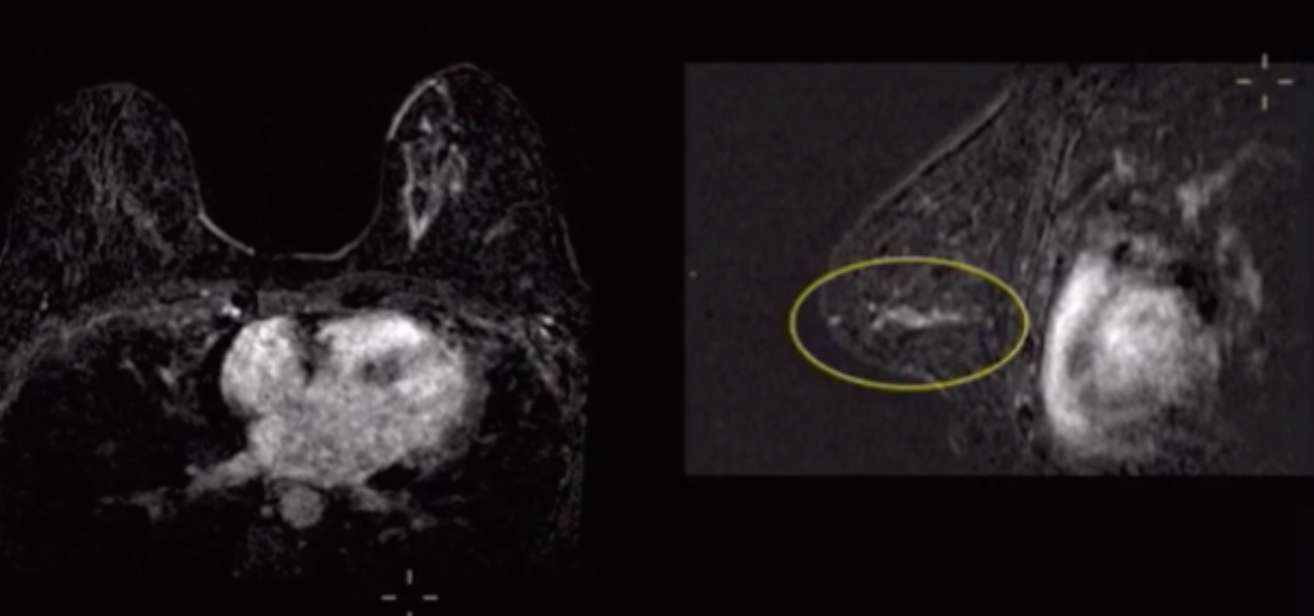

Non-mass enhancement

• Weird clump like area of enhancement

• Classified according to distribution

• Distribution of NME is the most predictive feature

• Segmental distribution has the highest PPV

• More concerning patterns

• Focal

• Linear

• Segmental

• Less concerning patterns

• Regional

• Multiple regions

• Diffuse

• If you see NME, think DCIS